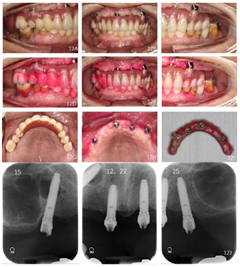

15、16、24、25、26、27缺失,已行可摘局部义齿修复;14-22Ⅲ度松动、17Ⅱ度松动、18Ⅰ度松动,牙龈萎缩,部分牙根暴露。36、47缺失,已行可摘局部义齿修复;45、46Ⅰ度松动。

口内及颌面部检查、根尖片、曲面体层片、CBCT检查。曲面体层片示11、21牙槽骨吸收至根尖1/3;12、14、17、22牙槽骨吸收超出根尖,12、22根尖圆形低密度影像;18、13、23、35、45、46牙槽骨吸收至根长2/3。诊断:1.上下颌牙列缺损。2.毛氏Ⅱ类5分类。3.广泛型Ⅳ期牙周炎。4.37深龋。

口外检查:颌面部大致对称,面下1/3前突,双侧颞下颌关节未见异常(图1)。

面照;F:正面照口内检查:15、16、24、25、26、27缺失,缺牙区牙槽嵴低、窄;14、12、11、21、22Ⅲ度松动、17Ⅱ度松动、18Ⅰ度松动,牙龈退缩,部分牙根暴露,前牙呈扇形分开,高笑线。31、32、41、42缺失,已行31、32、33、41、43烤瓷固定桥义齿修复(5单位);36缺失,37近中倾斜,近中邻面及远中邻

面可见黑色龋坏组织,质软,探诊、冷诊不适,叩诊(一);47缺失,缺牙区牙槽嵴低平,46牙龈退缩,根分叉暴露,

面可见白色充填物,完整。未见龈上结石,全口牙牙龈退缩,部分牙根外露。前牙重度深覆

重度深覆盖,双侧后牙无稳定咬合关系(图1)。

影像学检查:曲面体层片及CT检查显示11、21牙槽骨吸收至根尖1/3;12、14、17、22牙槽骨吸收超出根尖,12、22根尖圆形低密度影像,17根尖周低密度影像;18、13、23、35、45、46牙槽骨吸收至根长2/3;37近中及远中邻面可见低密度透射影像,近髓(图2)。